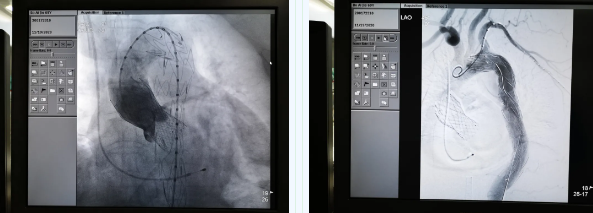

張金洲副院長關(guān)注著手術(shù)的每一個(gè)細(xì)節(jié),從建立軌道、跨瓣、釋放瓣膜、支架定位、造影和食道超聲確認(rèn),每一步都緊張而有序地進(jìn)行著。為了最大程度保障病人安全,心臟外科程亮副主任也帶隊(duì)建立動(dòng)靜脈入路,以備緊急體外循環(huán)。經(jīng)過團(tuán)隊(duì)每一位成員的密切配合,在近四小時(shí)的緊張奮戰(zhàn)之后,“TAVR TEVAR”復(fù)合手術(shù)順利完成;經(jīng)過造影和食道超聲證實(shí):人工主動(dòng)脈瓣無返流無瓣周漏、冠脈顯影良好,主動(dòng)脈覆膜支架無內(nèi)漏無移位。